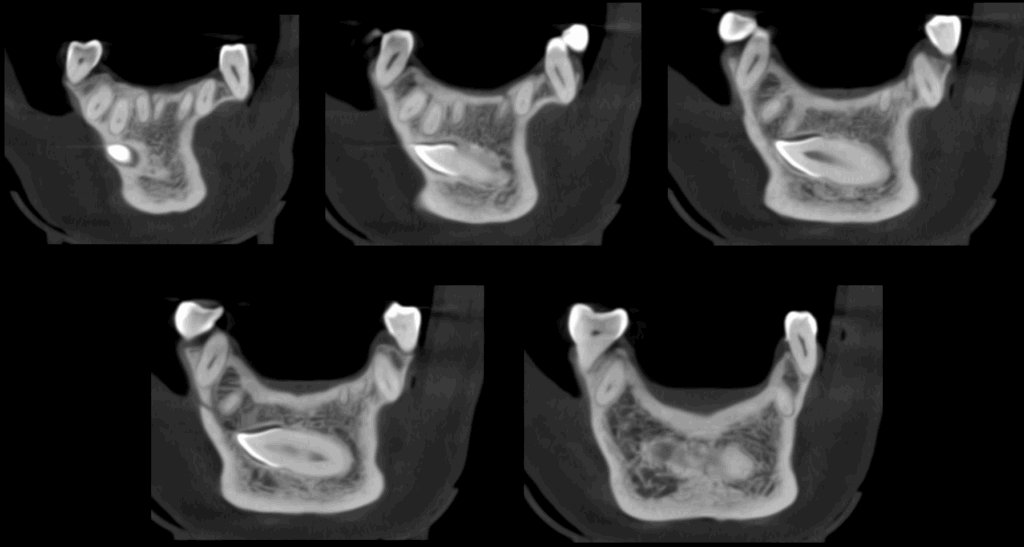

A la evaluación de la tomografía cone beam de campo mediano se puede observar que dicha pieza se encuentra caudal al ápice de las piezas 32, 31, 41, 42 y 43 con la porción coronaria en contacto y adelgazando la tabla ósea vestibular y la porción radicular se encuentra equidistante a ambas tablas óseas y la presencia de un foramen lingual. Se descartar cualquier relación con piezas dentarias vecinas

CORTES TRANSAXIALES

CORTES TANGENCIALES